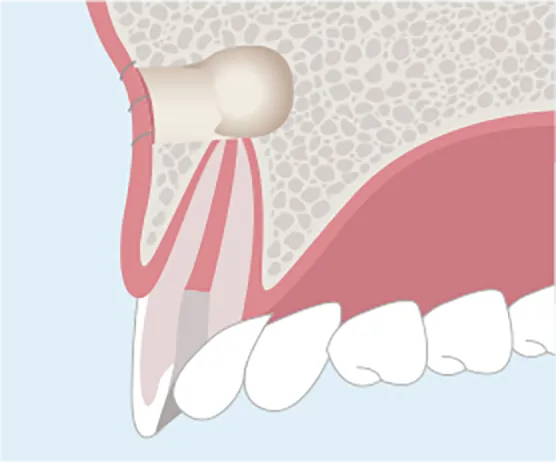

CASE 03

歯が歯茎に埋もれている場合

エクストリュージョン

むし歯や歯の破折で歯肉の中に歯が隠れてしまうと、被せ物を被せることができないので、歯を抜く選択肢をとらざるを得ない場合があります。こういった場合でも矯正の原理を使用して歯肉に埋もれた部分を露出させるエクストリュージョンを行うことにより、歯を残すことができます。

01

歯肉に歯が埋れてしまっている状態。

-

02

残った歯に矯正器具をつけて、ゆっくりと上に引っ張り上げます。

03

引っ張り出した部分に被せ物の土台が確保できるようになります。